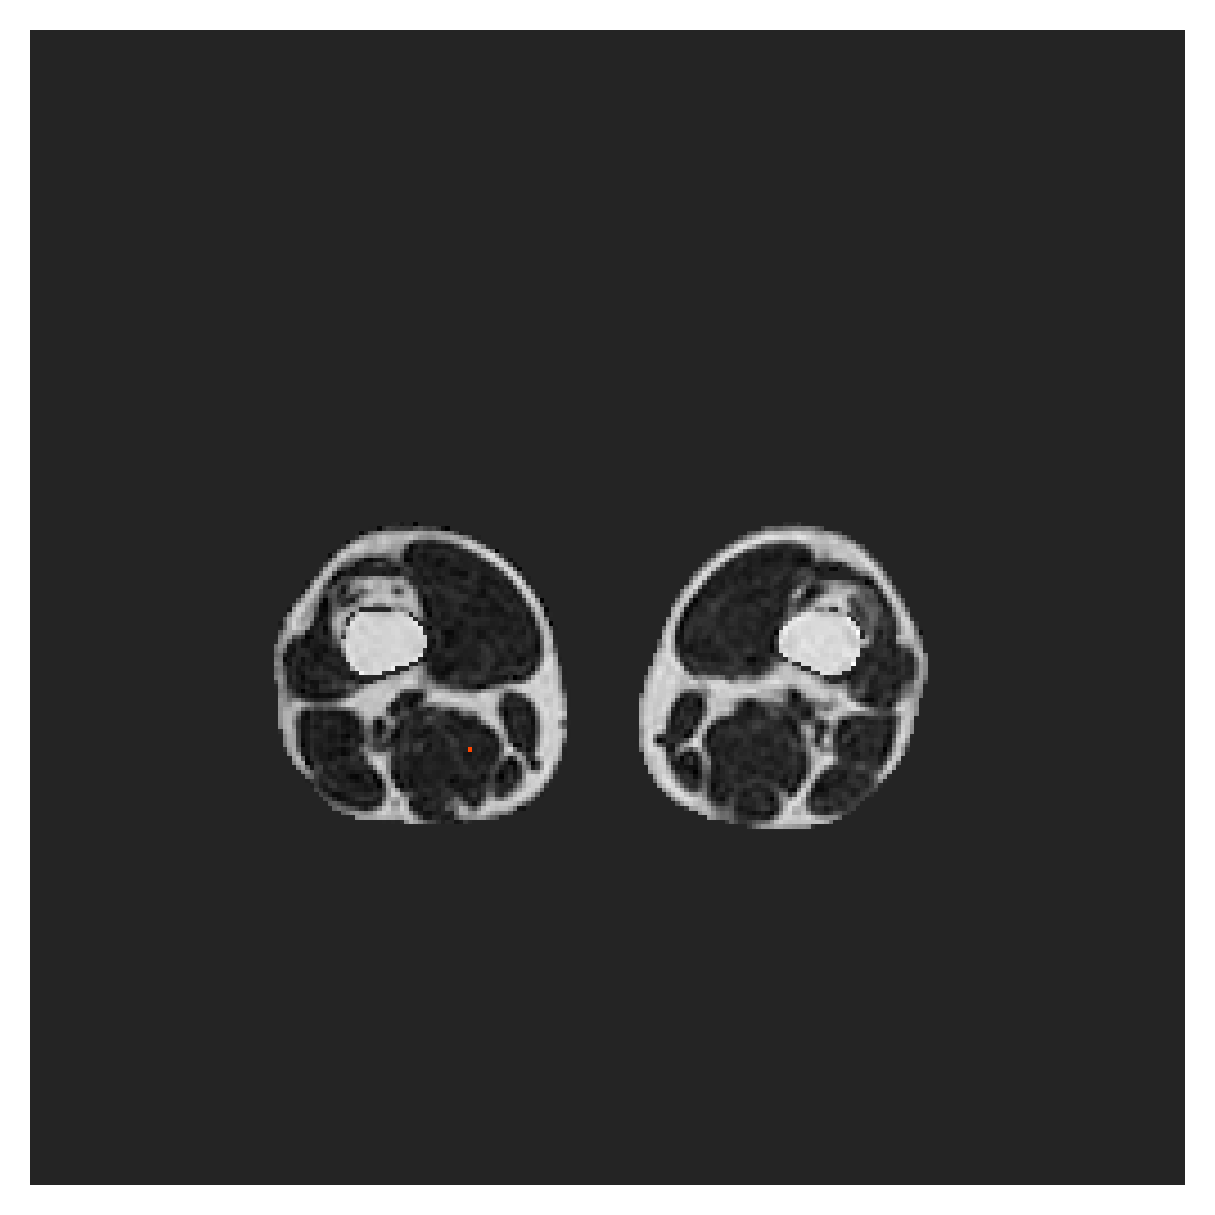

POEM

The Prospective investigation of Obesity, ENergy production and Metabolism (POEM) is a local (not currently publicly available; PI: L. Lind, see [22] for details) cohort of whole-body fat/water separated MR images. Full annotations of the liver, kidneys, bladder, pancreas and spleen are available for 50 subjects, providing a challenging segmentation dataset with heavily imbalanced classes of varying shapes. The resolution of the data is anisotropic, with reconstructed voxel size of in left-right, anterior-posterior and foot-head directions, respectively. For additional technical details regarding the acquisition and specifications of the images see [22].

The images contain two channels, one for water and one for fat content. For training, we normalize the volumes (per channel) and use 2D slices in the coronal plane, sized . The weak annotations are created synthetically, following the same procedure as described for the ACDC dataset.

5.2 Abdominal organ segmentation

Using 2D distance maps

In Table 3, the average DSC and HD95 results are shown (both using 2D and 3D distance maps) for the task of abdominal organ segmentation in POEM data (for boxplots see figures 8 and 9). We see that training with and (with distances calculated on 2D slices) performs comparably, while using and produces lower scores in both DSC and HD95 metric. On this dataset, the CRF-loss is able to compete with the boundary loss-based training strategies, even outperforming them on most classes. Most notably, all models trained with boundary loss appear to have a hard time segmenting the liver. We hypothesize this may be due to extremely severe class imbalance, as the liver covers a very large area compared to the rest of the classes. It is thus also more strongly affected by undersegmentations.

5.2.1 Qualitative comparison

In Figure 11 and 12 we show the same random slices in cases of calculating the boundary loss on 2D- and 3D-based distances, respectively. Comparing the two figures again indicates that the intensity-aware distances offer most improvement when calculated in 3D over 2D. The exception here is the MBD, which seems to even slightly degrade for most classes.